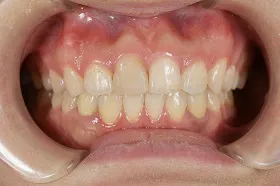

生まれつき歯が生えてこなかったケース

■治療前:生まれつき下顎左右前歯がなく隙間がある

■治療後:矯正治療後、下顎左右3番の2本にインプラント治療

| 主訴 | 生まれつき歯がなく隙間があり、審美障害・咀嚼機能障害がある |

| 治療方法 | インプラント治療 + 矯正治療 |

| 治療期間 | インプラント治療 約6ヶ月 |

| 通院回数等 | インプラント治療 約6回 |

| 費用 | 約94万円(税込) |

| リスク・副作用 | 術後の腫れ・痛み |